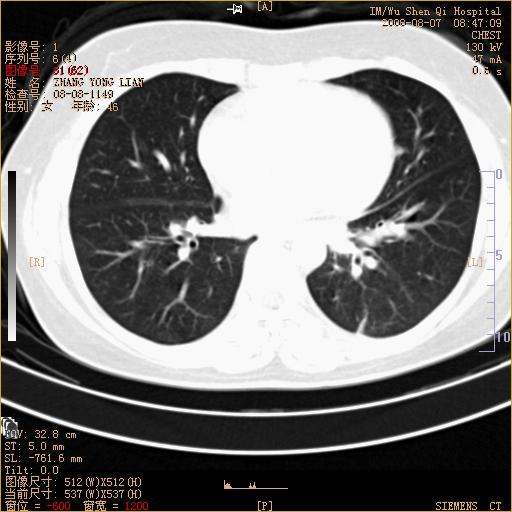

标题: CT15050:女,46岁,咳嗽胸痛一月余 [打印本页]

纵隔窗没发全,左下肺近胸膜处结节。有长毛刺,纵隔淋巴结增大,不排除恶性病变。

考虑肺癌

考虑左肺下叶后基底段周围型肺癌伴纵隔淋巴结转移可能性大。

左下肺ca并纵隔及左肺门区淋巴结转移。

1)考虑左肺下叶后基底段周围型肺癌伴纵隔淋巴结转移。2)脾内低密度灶,性质待定;不排除转移瘤可能。

考虑左肺下叶后基底段周围型肺癌伴纵隔及肺门淋巴转移。